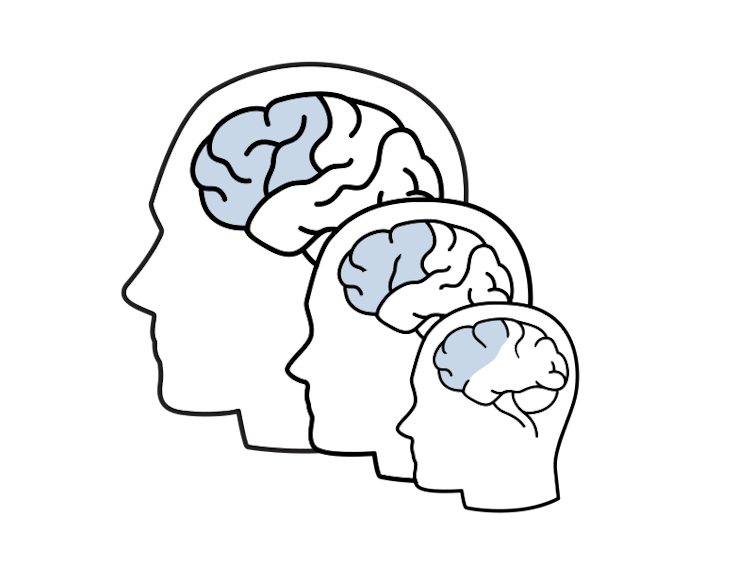

As recently as a few decades ago, it was still thought that the brain only grew during childhood and did not change much after that. However, newer brain imaging studies show that the brain does in fact mature past childhood and that these changes continue well into the twenties and thirties.

During adolescence, the grey matter of the brain (where the nerve cells sit) is slowly shrinking, while white matter (the wiring between nerve cells) is still growing. These changes in the brain indicate that the neural networks are further refining their functions and connections, getting rid of what is irrelevant and reinforcing what is important.

These changes are more accentuated in some areas of the brain than others, namely the ones hosting the higher-order cognitive functions. The prefrontal cortex, in particular, shows the most protracted development, lasting well into a person’s twenties. This is the part of the brain that hosts the most sophisticated of our abilities – from making complex decisions to planning and suppressing unwanted urges.

In other words, in adolescence, many of these sophisticated brain functions are still in development. This may explain why teenagers sometimes struggle to use complex reasoning skills or why they act on impulse and take unnecessary risks.